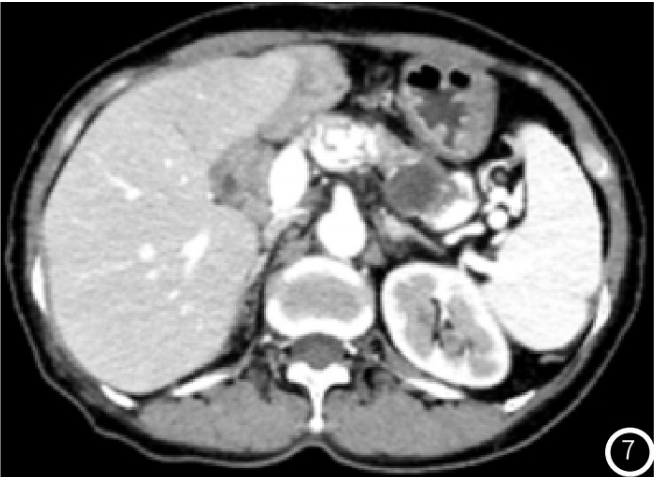

示胰头类圆形低密度结节,大小约14mm×12mm,增强扫描动脉期结节明显均匀强化(图1),强化程度高于正常胰腺实质,静脉期强化减低,边界清;术后4年常规胸腹部CT

图7 随诊CT增强示胰腺病灶较前缩小,实性成分减少,囊变坏死明显;